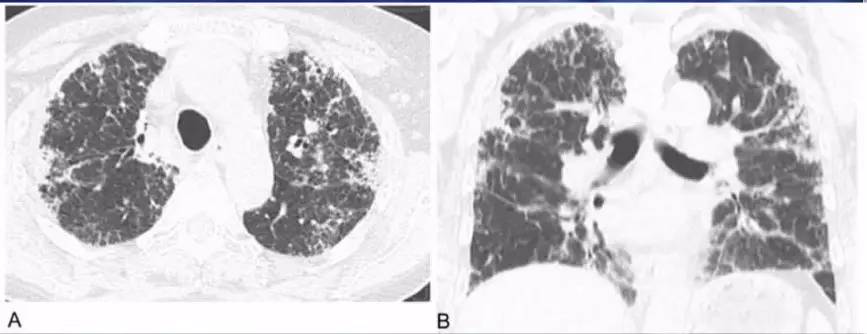

慢性期胸部CT表现为:两肺内不规则的线样、网状、或蜂窝状阴影结节影,靠近胸膜分布局部有磨玻璃样改变,并可见牵张性支气管扩张(图8)。

图 8: OHP慢性期胸部CT表现